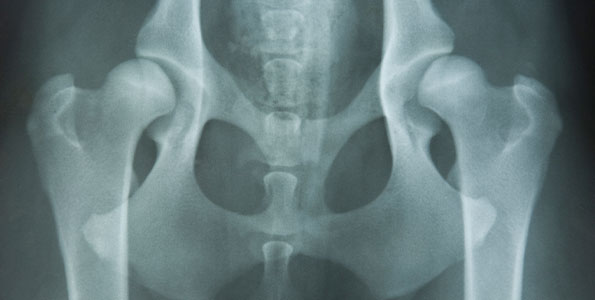

Hallym Institute for Skeleton Aging Research

Hallym Institute for Skeleton Aging Research was established to perform a role for medical advancements and pioneering in various clinical fields including artificial joints, geriatric fractures, and arthritis by operating molecular biological, biological, biomedical engineering, and clinical research systems regarding aging related musculoskeletal diseases related to aging. In the basic research field, the institute conducts studies on the in vivo responses to biomaterials, the discovery of substances that promote bone formation, and the development of therapeutic agents for arthritis, aiming to overcome osteolysis following artificial joint replacement. On the clinical side, it contributes globally to the treatment of skeletal diseases by improving joint surgery techniques, providing basic and clinical training programs in developing countries, and supporting the enhancement of clinical care systems.